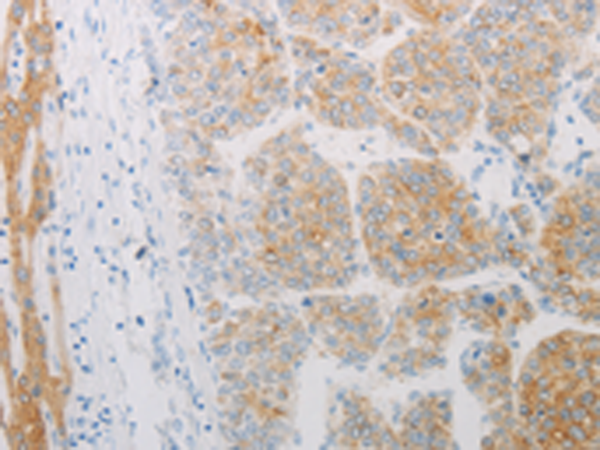

分类: 科研抗体货号: P10649别名: BETA3AR应用: IHC反应种属: Human